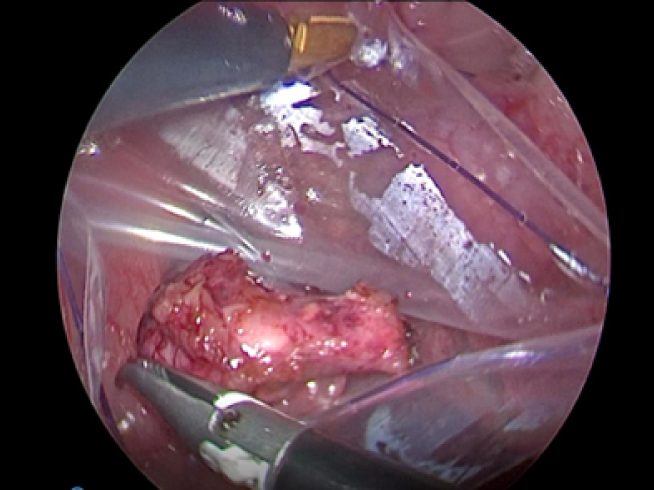

離断した副腎をバッグに入れて外へ出します。

出血もほとんどなくとても綺麗に摘出することが出来ました。 今回の手術時間は短く約45分でした。 病理検査の結果、副腎皮質癌という悪性腫瘍でした。 とても元気すぎてすぐに退院していきました。

実際の手術風景です。